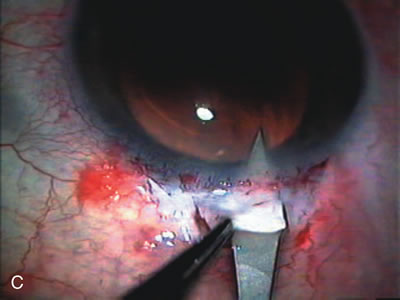

CATARACT EXTRACTION ALONE REDUCES IOP IN MOST EYES WITH ANGLE-CLOSURE GLAUCOMA

Uncomplicated cataract extraction substantially reduces IOP, along with the number of postoperative glaucoma medications in eyes with angle-closure glaucoma.146,147 When preoperative gonioscopy reveals PAS, along with adjacent areas of appositional closure, lens extraction alone in select cases may be a reasonable alternative to filtration surgery.148,149 Phacomorphic angle-closure disease due to enlargement of the lens with progressive angle crowding is eliminated following lens extraction. The width and depth of the anterior chamber angle in eyes with angle-closure glaucoma increases significantly after cataract extraction with IOL implantation and becomes similar to open-angle glaucoma and normal eyes.150,151 (Fig. 5). Combining phacoemulsification, IOL implantation, and limited goniosynechialysis is effective in the treatment of cataract and chronic angle-closure glaucoma.152 Phacoemulsification with implantation of a foldable IOL is more effective in reducing IOP and improving visual acuity than surgical peripheral iridectomy in eyes with acute angle-closure glaucoma.153

Fig. 5. Anterior chamber angle changes associated with lens extraction and PCIOL This 65-year-old Vietnamese woman has a long-standing history of chronic angle-closure glaucoma treated with laser peripheral iridectomy. The optic nerve demonstrated mild glaucomatous damage and IOP was moderately controlled on two antiglaucoma medications. The cataract was removed through temporal clear corneal phacoemulsification with foldable acrylic IOL. A. Symptomatic cataract in narrow-angle glaucoma eye with patent iridectomy. B. Intraoperative goniophotograph showing crowding of angle with increasing narrowness due to phacomorphic component. C. Intraoperative photograph showing temporal clear corneal approach with IOL in the capsular bag. D. Intraoperative goniophotograph demonstrating deepening of chamber angle following lens extraction. Proposed theories for IOP reduction following lens extraction with complete wound closure:

1. Anterior chamber deepening with improved access to trabecular meshwork

2. Increase in traction on the trabecular meshwork

3. Improved outflow facility mediated by an increase in prostaglandin release

4. Reduction in aqueous humor production

5. Atrophy of ciliary body processes

6. Goniosynechialysis due to intraoperative over deepening of AC with viscoelastic

7. Relief of undiagnosed pupil block